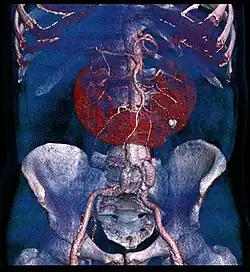

Als Hufeisenniere bezeichnet man eine angeborene Fehlbildung mit teilweiser Verschmelzung beider normalerweise getrennt liegender Nieren, so dass sie die namensgebende Form eines Hufeisens bilden. Es handelt sich nicht um eine Krankheit, sondern um eine anatomische Normabweichung (Anomalie).[1]

Die beiden Nieren sind am häufigsten am unteren Pol durch eine Bindegewebs- oder häufiger durch eine Parenchymbrücke miteinander verbunden. Dadurch ist die Achslage der Nieren, welche normalerweise von oben-innen nach unten-außen verläuft, verändert, gleichzeitig ist die Drehung des Hohlsystemes nach innen (medial) ausgeblieben, so dass das Nierenbecken nach vorne (ventral) weist. Die Harnleiter gehen infolge der veränderten Lage des Nierenbeckens meist weiter kranial ab und müssen „über den Berg“ der Parenchymbrücke verlaufen.[3]

Zur Diagnosestellung einer Hufeisenniere eignen sich alle üblichen bildgebenden Verfahren, allen voran die Sonografie, die Computertomografie genauso wie die Magnetresonanztomografie, aber auch konventionelle Röntgen-Untersuchungen wie die Urografie.